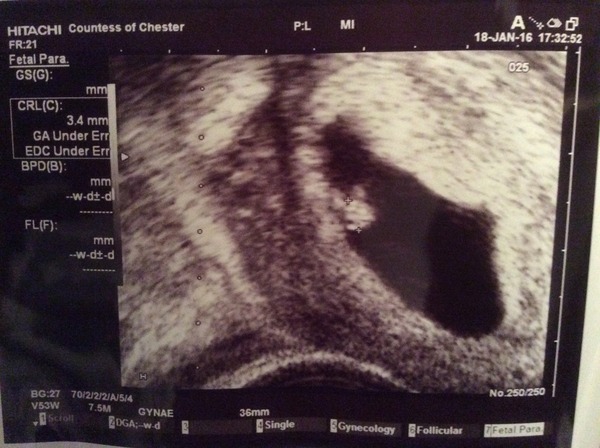

Flat my consultant said his minimum was 7mm - he has had pregnancies in women with 6.5mm, but he wouldn’t want to risk transferring a good quality embryo into a suboptimal uterine environment. I was at 7.6mm the day before trigger, and regressed to 6.4mm on EC day, so I’m desperately hoping my lining doesn’t decide to spontaneously combust again like last time!